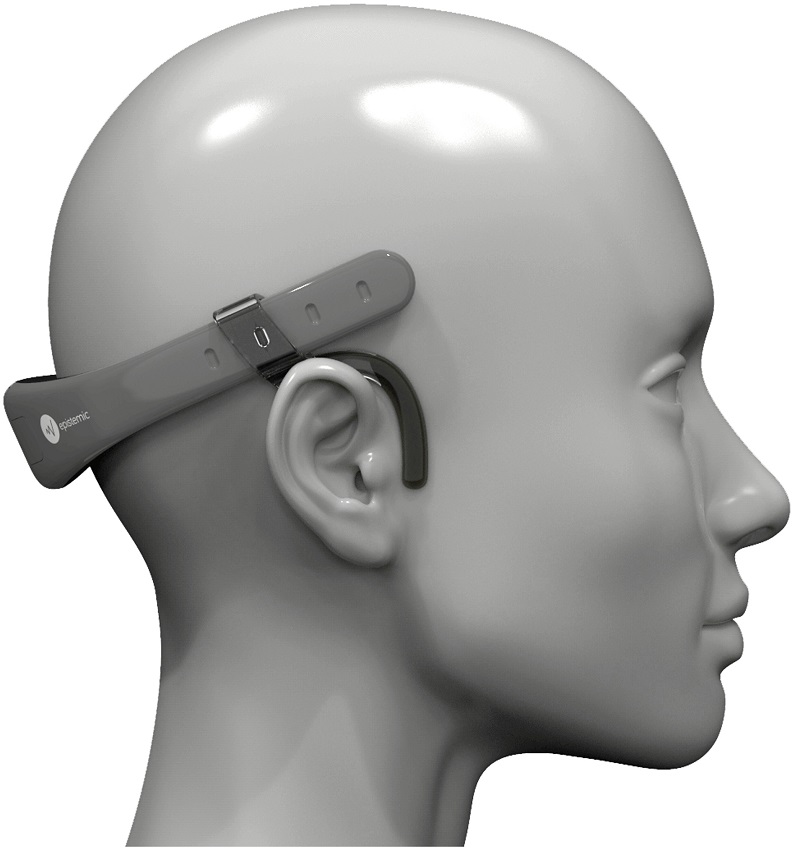

A partir do aplicativo, a Epistemic está desenvolvendo o Aurora, um aparelho no formato de um fone de ouvido esportivo que prevê crises epilépticas. O equipamento conta com uma novidade, que são eletrodos secos (sem a necessidade de usar substâncias pastosas, como é comum em hospitais), que produzem um eletroencefalograma e, diante de alguma variação que indique a possibilidade de crise, é enviado um alerta a paciente e cuidadores e familiares autorizados.

“Pelo formato, o Aurora é indicado para ser utilizado atrás da cabeça durante o dia e na testa à noite, para não atrapalhar o sono e o posicionamento no travesseiro. Ainda passa por testes clínicos para ir ao mercado, mas já apresenta resultados positivos. O Epistemic App desenvolvido no Samsung Creative Startups tinha avanços, como a possibilidade de se registrar uma crise com um simples clique no raio no canto superior direito da tela inicial, além de oferecer dicas nutricionais de profissionais especializados e as melhores opções no momento de agir diante de uma crise. O Aurora é uma evolução nesse auxílio ao controle de epilepsia”, explicou Paula Gomez, CEO da Epistemic.